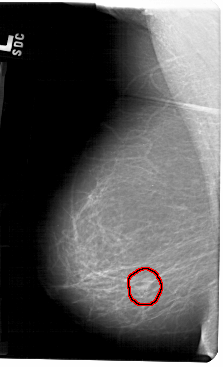

FILE: A_1271_1.LEFT_MLO.OVERLAY

TOTAL_ABNORMALITIES 1

ABNORMALITY 1

LESION_TYPE MASS SHAPE OVAL MARGINS CIRCUMSCRIBED-OBSCURED

ASSESSMENT 4

SUBTLETY 4

PATHOLOGY BENIGN

TOTAL_OUTLINES 1

BOUNDARY